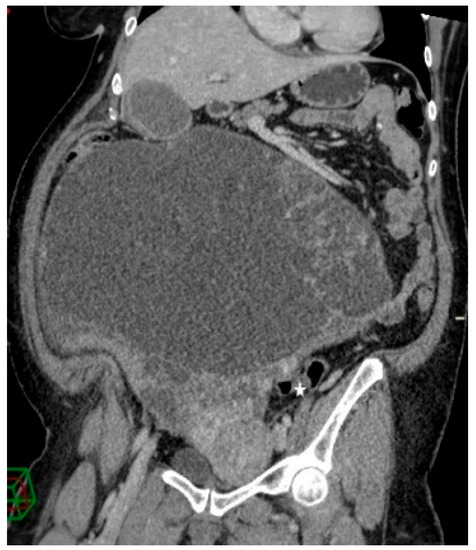

Figure 3.

Contrast-enhanced abdominopelvic CT—curved reformation shows a large abdominopelvic cystic multiseptated mass, with a mass effect on the sigmoid colon (white star).